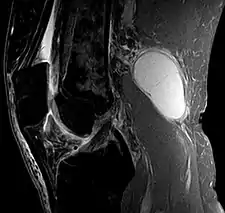

- Baker's cyst on MRI, sagittal image